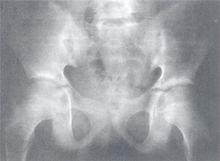

影像學

早期可見關節附近軟組織腫脹,骨骺部骨質稀疏。晚期嚴重關節炎患者可見骨表面破壞,關節腔變窄,骨囊性變,骨膜反應及關節半脫位等。